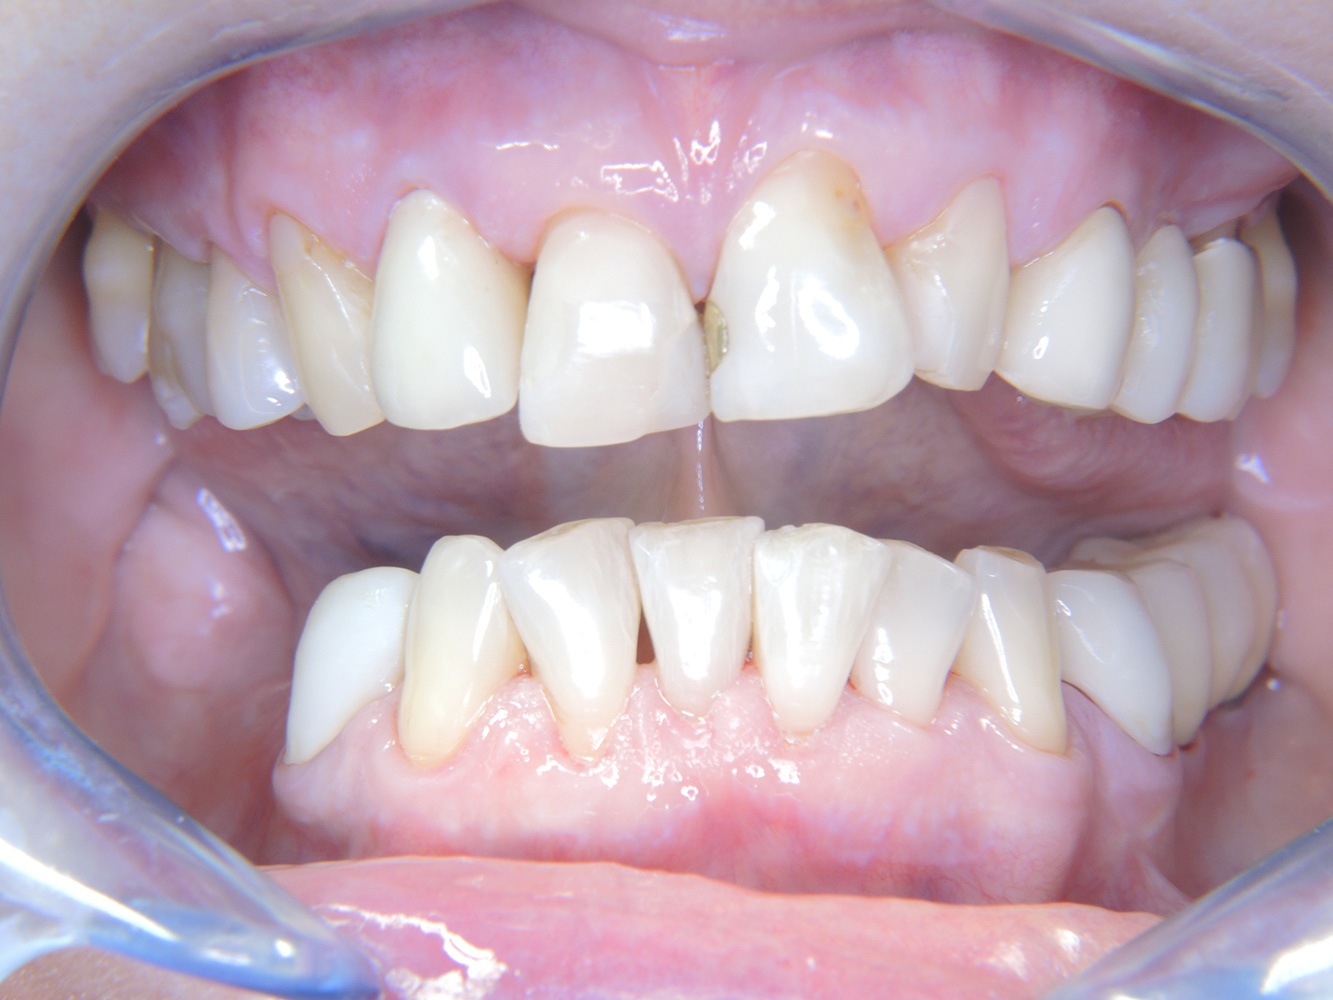

Die 68-jährige Patientin hat keine zahnmedizinisch relevanten allgemeingesundheitlichen Vorerkrankungen oder Medikation, auch aus dem Lebensstil ergibt sich kein besonderes Risiko. Die Patientin hat zwei Implantate (3. Quadrant, seit fünf Jahren) sowie eine parodontale Vorerkrankung (Parodontitis Stadium IV, Grad B) mit Zahnverlust. Derzeit zeigen sich stabile parodontale Verhältnisse, jedoch erhöht Parodontitis maßgeblich die biologischen Komplikationen bei Implantationen und es droht der Implantatverlust (21).

Trotz der stabilen Verhältnisse sollten auch bei dieser Patientin die Motivation/Instruktion nicht vernachlässigt werden. Besonderes Augenmerk gilt dem Erlernen der richtigen Implantatpflege. Gerade hier kann eine gute häusliche Pflege einen wichtigen Anteil an der langfristigen Stabilisierung der Mund- und Implantatgesundheit haben.

In der Instrumentierung gilt im Bereich der Implantate eine besondere Vorgehensweise. Zum Erhalt der Implantatoberfläche bei gleichzeitig effektiver Reinigung ist die Wahl passender Pulver und Instrumente ausschlaggebend, wie etwa der gezielte Einsatz von Pulverstrahlgeräten mit speziellen Paro-Spitzen. Die Wahl des geeigneten Pulvers kann bedarfs- und risikogerecht erfolgen, beispielsweise kann neben dem passenden Abrasionsgrad auch auf diätische Anforderungen (u. a. zuckerfrei, salzarm) eingegangen werden.